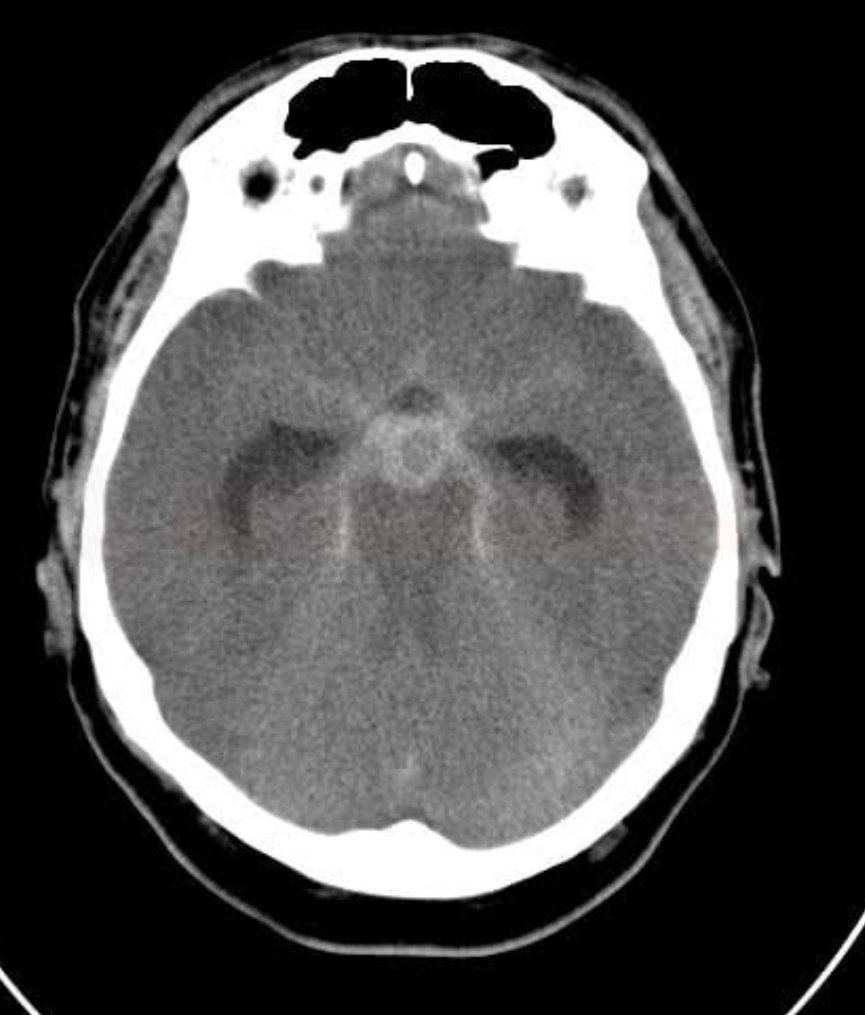

Your diagnosis!!!